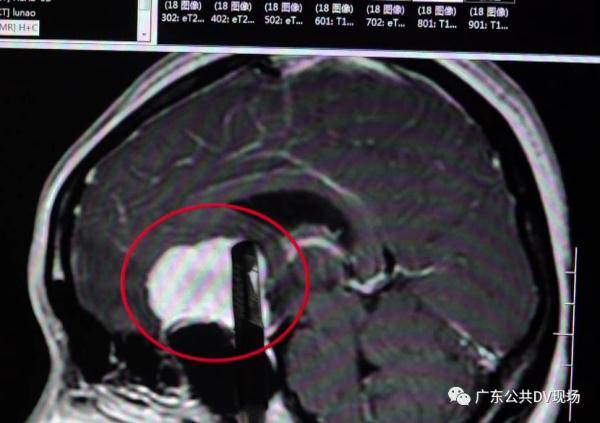

脑部肿瘤也被查明

鞍区脑膜瘤

文章图片

医生介绍

因为视神经被肿瘤严重压迫

而且肿瘤还包裹着大脑前的动脉

手术难度非常大

周密手术完成

医生从张姨的脑部取出的肿瘤

居然有鸡蛋般大小

直径约4公分